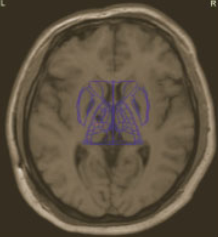

Burke-Fahn-Marsden rating scale26 (BFMRS) score was: 104/120. A T2 weighted brain Magnetic Resonance imaging (MRI) scan showed hypersignal bilaterally involving both pallida, mostly affecting the most medial part (Figure 2). Treatment attempts with Trihexyphenidyl, Carbidopa-Levodopa, Carbamazepine, Clonazepam, Phenytoin and Baclofen were unsuccessful. Botulinum toxin injections provided some relief of the muscular contractions but rapidly became ineffective considering the importance of dystonic movements. The family gave informed consent for DBS surgery. As the main output of the pallidum is the ventrolateral thalamic nuclei (Voa) and the centromedian-parafascicular nucleus,30,34 we decided to target Voa for DBS and hoped it would act directly on the last distal part of the retroactive feedback to the motor cortex from GPi.

Figure 2 Pre-operative MRI showing selective necrosis of the Globus Pallidus interna, predominantly on the right side (above images are in radiological view).